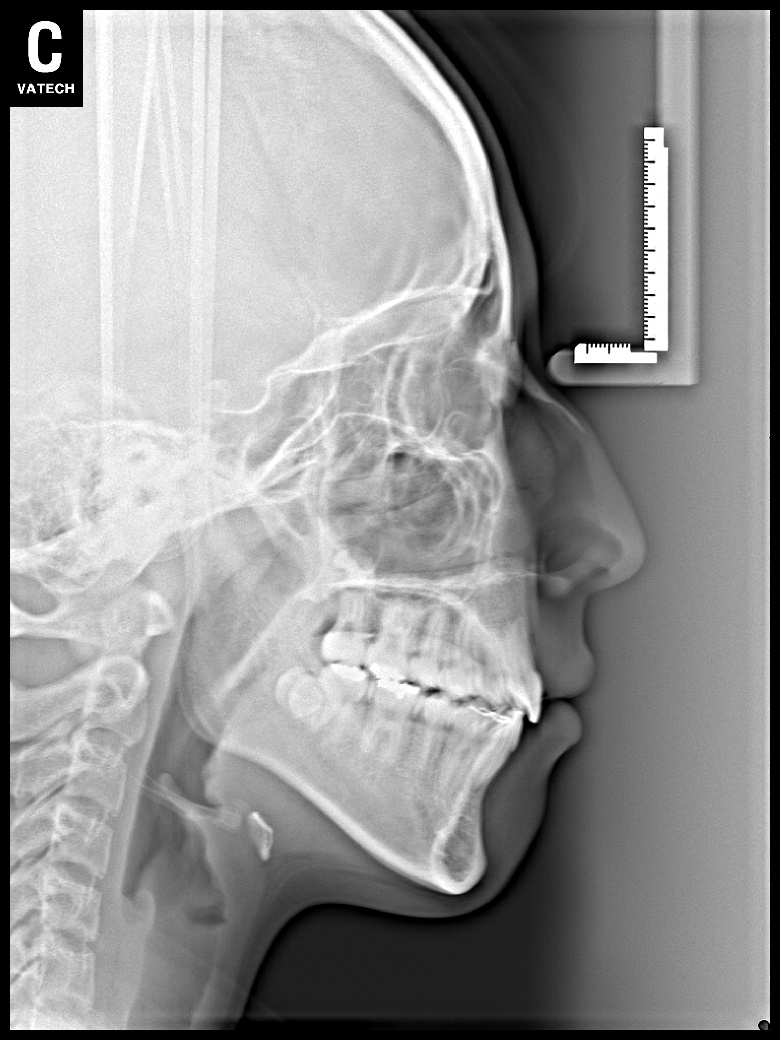

치료 전 사진입니다.

치료 후 사진입니다.